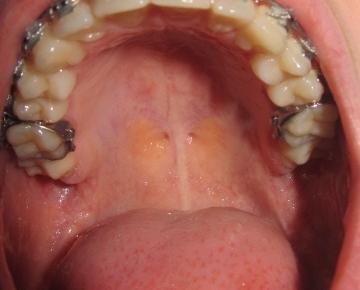

Offene stelle am gaumen. Sie haben ein zu hartes Brötchen mit Kanten und schon ist es passiert die Haut und weiteres Gewebe werden im Mundraum verletzt. Die Heizungsluft trocknet die Lippen aus mit der Zahnseide hat man sich das Zahnfleisch verletzt oder es kribbelt schon wieder ein Herpesbläschen eine kleine Wunde im Mund entsteht schnell. Einer Woche eine offene Stelle am Gaumen direkt hinter den Zähnen.

Diese wird genau untersucht. Eine Entzündung am Gaumen fällt meist durch eine schmerzhafte Schwelllung und Rötung auf. Beschwerden am gaumen bei zahnschmerzen hintergrund können zahnschmerzen sein die sich auf den gesamten mund rachen bereich ausdehnen und damit auch den gaumen betreffen können einleitung eine entzündung am gaumen fällt meist durch eine schmerzhafte schwelllung und rötung auf.

Die sorgt dafür dass aus dem Zucker im Honig Wasserstoffperoxid. Zu unterscheiden sind die Entzündung an der Schleimhaut des Gaumens selbst und Entzündungen am Zäpfchen den Mandeln im Gaumensegel.

Recurrent aphthous stomatitis oral apthous ulcers sind kleine weiße oder rote offene Stellen oder Geschwüre der Mundschleimhaut der Zunge oder des Gaumens. Die sorgt dafür dass aus dem Zucker im Honig Wasserstoffperoxid. Entzündung am Gaumen - Dr-Gumpert. Diese kann aufgrund von Verletzungen Infektionen allergischen Reaktionen oder gar Verbrennungen auftreten. Eine Entzündung am Gaumen fällt meist durch eine schmerzhafte Schwelllung und Rötung auf. Beschwerden am Gaumen bei Zahnschmerzen Hintergrund können Zahnschmerzen sein die sich auf den gesamten Mund-Rachen-Bereich ausdehnen und damit auch den Gaumen betreffen können Einleitung Eine Entzündung am Gaumen fällt meist durch eine schmerzhafte Schwelllung und Rötung aufDiese kann aufgrund von Verletzungen Infektionen allergischen. Ich hoffe ich bin im richtigen Forum. Der Begriff kommt aus dem Griechischen und bedeutet Schwämmchen. Beim Kauen oder bei Kontakt mit Fruchtsäure.

Hallo ich habe seit ca. Offene stelle am gaumen was tun Gaumenschmerzen. Eine Entzündung am Gaumen fällt meist durch eine schmerzhafte Schwelllung und Rötung auf. Zu diesem Zweck eignen sich Kräuter wie Johanniskraut Kamille Lindenblüten und Nelken die zu einem Tee zubereitet werden. Beim Kauen oder bei Kontakt mit Fruchtsäure. Eine leichte Gaumenreizung kann man schon von zu heißen Nahrungsmitteln bekommen. Aphthen sind eine der häufigsten Krankheiten der Mundschleimhaut.